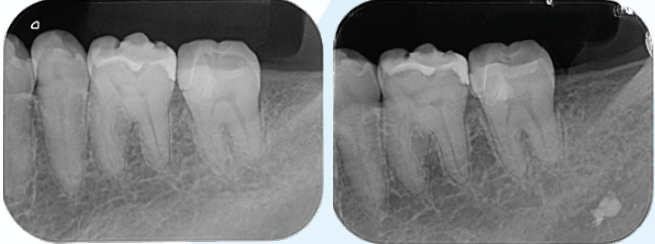

術後7年経過、露髄した髄角部には、デンティンブリッジが形成されMTAセメントと歯髄の間に硬組織が認められる(図8)術直後と7年後の比較)。口腔内の状態は多少の咬耗は認めるが、ナイトガードを使用することでパラファンクションに対応しながらメンテナンス継続中。

(図8)近心髄角付近に新たに形成された象牙質様の硬組織を示す不透過像を認める

2024/11/23 2017/11/9